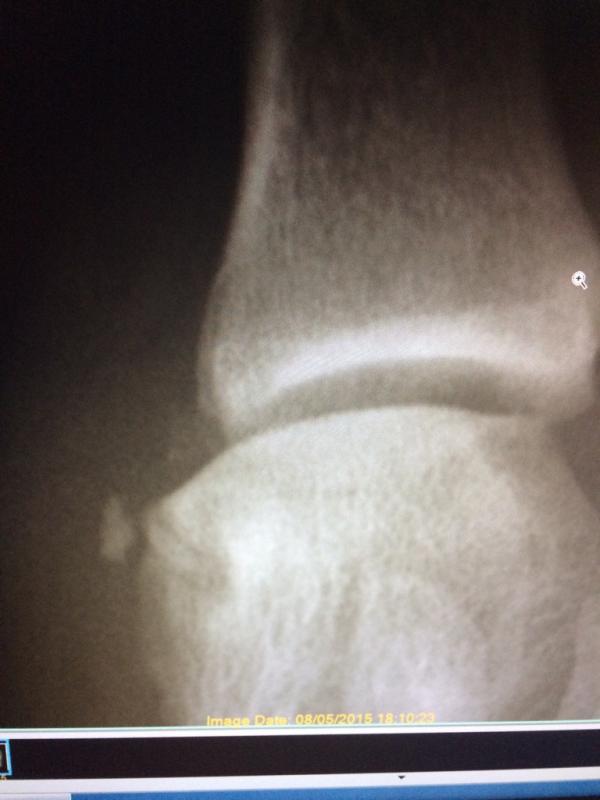

Yah.....I'm feeling really effing old today! Never would of guessed such a small break by the joint would stop we from walking....seriously WTF

Attachment 56504